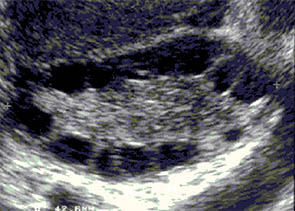

- Polycystic ovaries are seen by ultrasound and usually show 8 to 10 small follicles in the periphery of the ovary revealing a “string of pearls” appearance.